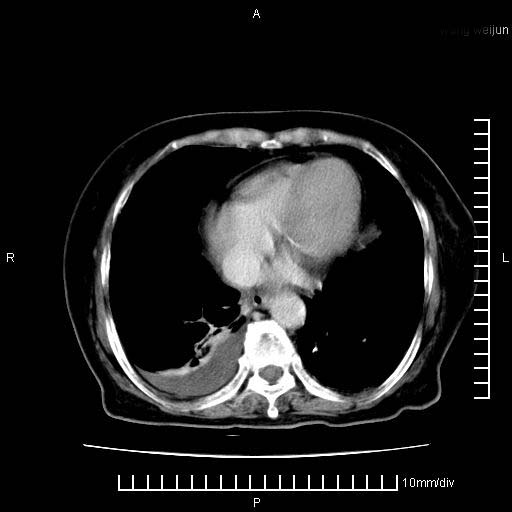

3。右胸腔积液,伴右肺下叶部分萎陷。

1)考虑胰腺癌并胰腺假性囊肿形成。2)肝内低密度灶,不排除转移。3)右肾盂积水。4)腹水。5)右侧胸腔积液并右肺下叶部分膨胀不全。

考虑胰腺ca伴腹膜腔转移、肝左叶转移、右肾积水。右胸腔积液。

考虑胰腺ca伴腹膜腔转移、肝左叶转移、右肾积水。右胸腔积液。支持